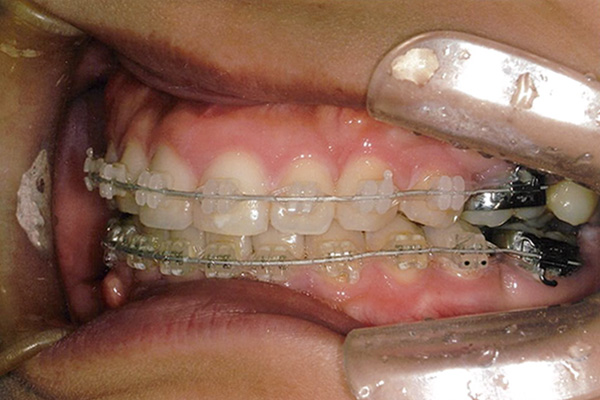

20代 女性

| 症状 | 下顎第一大臼歯の欠損 |

治療経過

10ヶ月後